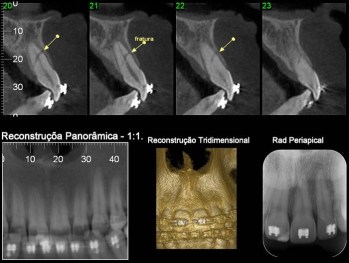

Novas tecnologias, instrumentos e materiais conduziram a um melhor diagnóstico e a uma maior previsibilidade do tratamento endodôntico. A Tomografia Computadorizada por Feixe Cônico (TCFC) tem um papel importante no diagnóstico e planejamento destes tratamentos, pois permite uma visualização 3D e elimina as sobreposições de estruturas.

A Tomografia Computadorizada passa a auxiliar no tratamento endodôntico, no planejamento pré-cirúrgico, na identificação da morfologia e anatomia dos canais, na detecção de canais não visíveis ou acessórios, na realização de medições precisas das distâncias dos canais, na avaliação das fraturas ou traumas das raízes, nas análises e caracterização externa e interna das reabsorções radiculares assim como de reabsorções cervicais, na deteção da diferença entre cistos e granulomas ou ainda em outros tipos de lesões de cavidade.

A morfologia das raízes e a topografia óssea podem ser observadas na renderização 3D das imagens, assim como o número de canais radiculares, a sua divergência ou convergência, o seu verdadeiro tamanho, localização e extensão das lesões periapicais e a qual a raiz existe uma lesão associada.

Desta forma, podemos concluir que a TCFC conduz a um melhor planejamento da cirurgia endodôntica, levando a uma melhoria dos resultados e objetivos. A seguir, para ilustrar, apresentamos alguns casos, onde podemos evidenciar a utilização da TCFC: